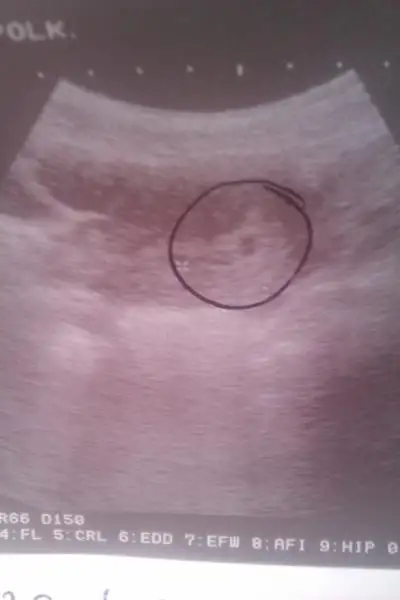

oyle yapmaya çalışıyorum ama elde değil ultrasın görüntüsü bu şekilde belki anlarsınız die gösteriyorum Eki Görüntüle 721763 Eki Görüntüle 721763